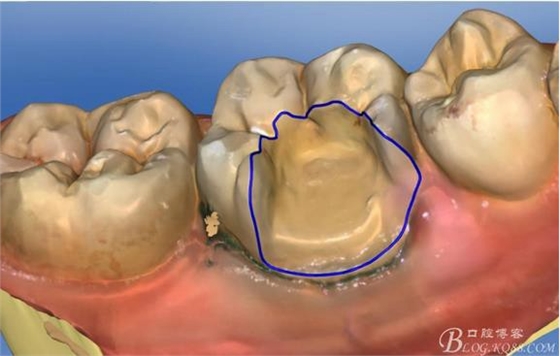

畫線是最關(guān)鍵的,線畫不好制出的修復(fù)體會出現(xiàn)邊緣缺損 或多 或少,醫(yī)生和技術(shù)配合

掃描 畫線 準(zhǔn)備研磨

我們現(xiàn)在用的瓷塊有四種:義獲嘉 VITA e-MAX

西諾德公司的

這位客人用的是琥珀瓷適

用于后牙嵌體 全冠高嵌體 前牙的瓷貼面首選